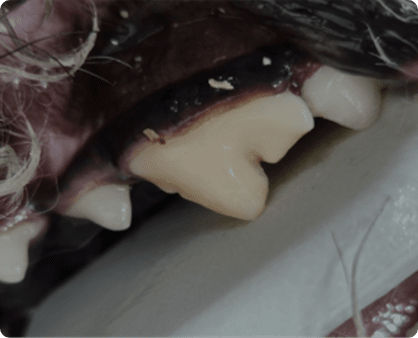

성장 중인 개체에서 자연 발치 되지 않고 유치가 남은 상태

성장 등의 문제 혹은 선천적 문제로 인해

치아 교합이 바르지 못한 상태